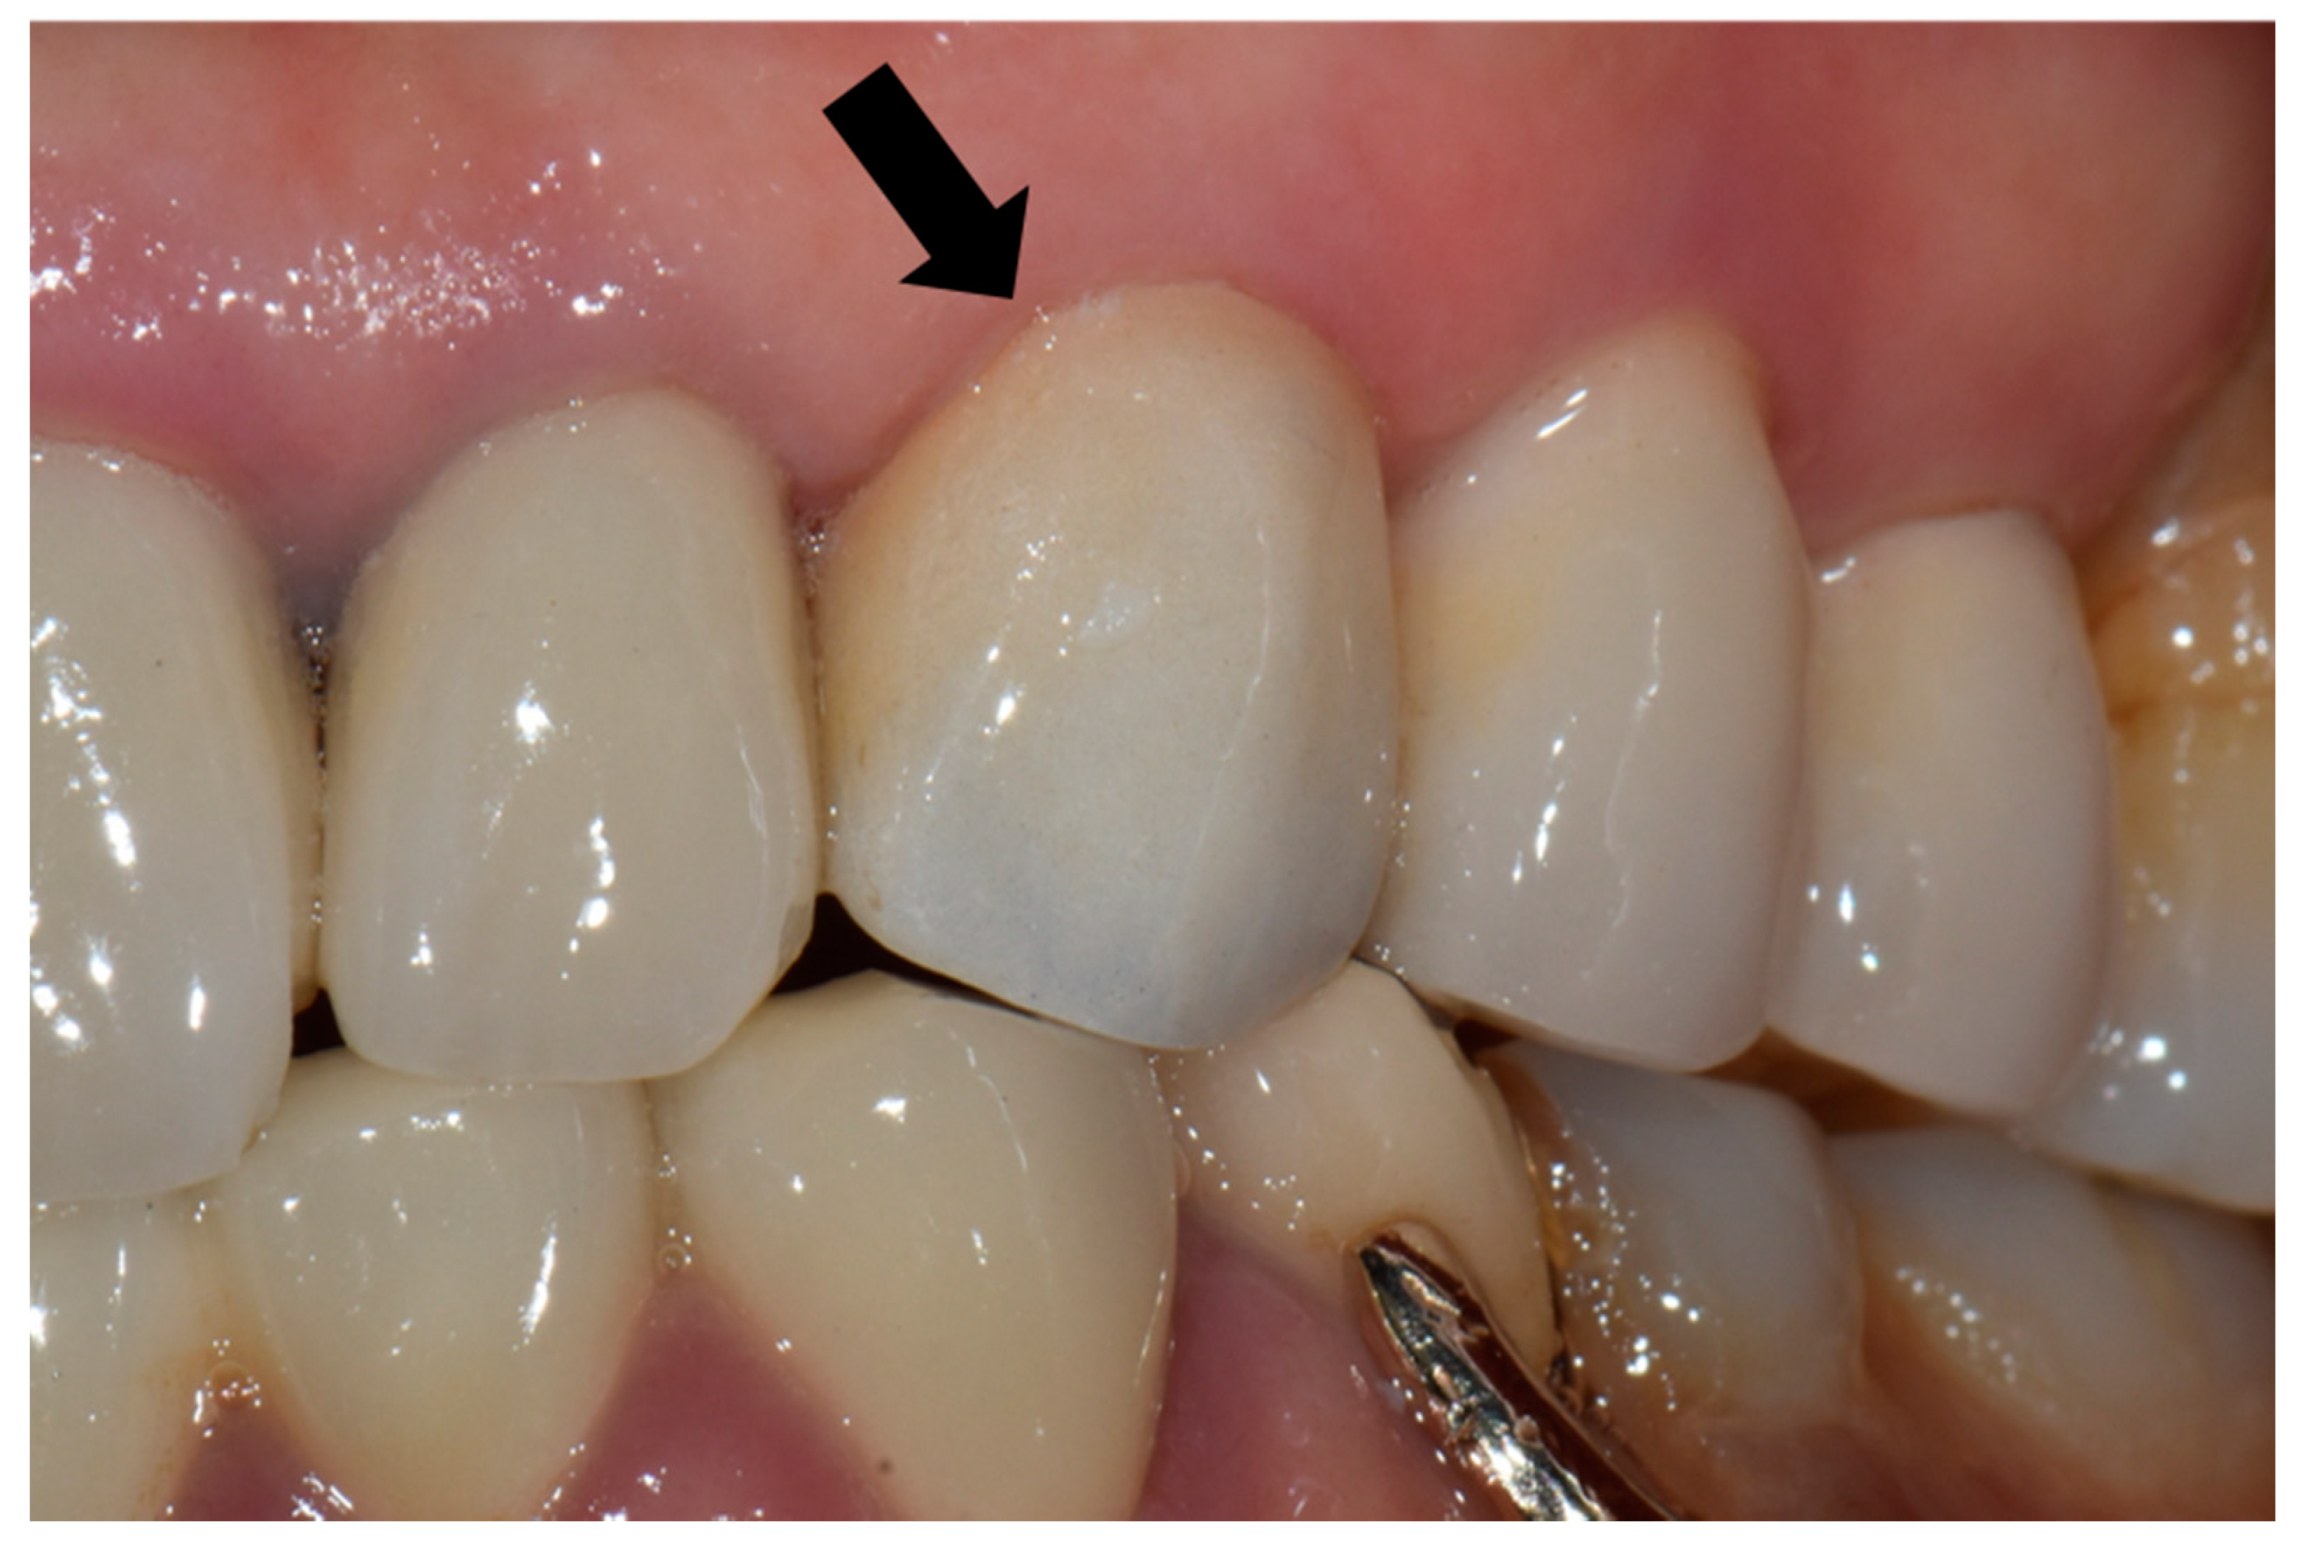

For each case, the master cast was fabricated with type III dental stone (Snow rock dental stone, DK Mungyo, Gimhae, Korea) and digitally scanned using a model scanner (3Shape D2000, 3Shape, Copenhagen, Denmark). All restorations were designed by dental technicians with 15 years’ experience, using the CAD software (3Shape CAD Design software, 3Shape, Copenhagen, Denmark) following the manufacturer’s instructions. The anatomically contoured zirconia crowns were milled (Cori TEC one, imes-icore, Eiterfeld, Germany) from fully-sintered (Y, Nb)-TZP blocks (Perfit-FS, Vatech MCIS, Gyeonggi-do, South Korea). For optimal shade reproduction, the milled restorations were treated with the zirconia-coloring liquid at 780 °C for 1 min with a firing rate of 45 °C/min using a sintering furnace (Austromat D4, Dekema, Freilassing, Germany). At the third visit, the definitive restoration was carefully evaluated on each participant’s abutment regarding the shape, adaptation, color match, proximal contact, and occlusion (Figure 1). If adjustments were needed, it was conducted using a fine-grained diamond bur with a high-speed handpiece. Resin-modified glass ionomer cement (GC FujiCEM 2, GC, IL, USA) was used to cement the crown in place. The participants were instructed to revisit the clinic for follow-up, as scheduled.

Figure 1.

Fully sintered (Y, Nb)-TZP (tetragonal zirconia polycrystal) crown was placed on the maxillary left canine (black arrow).